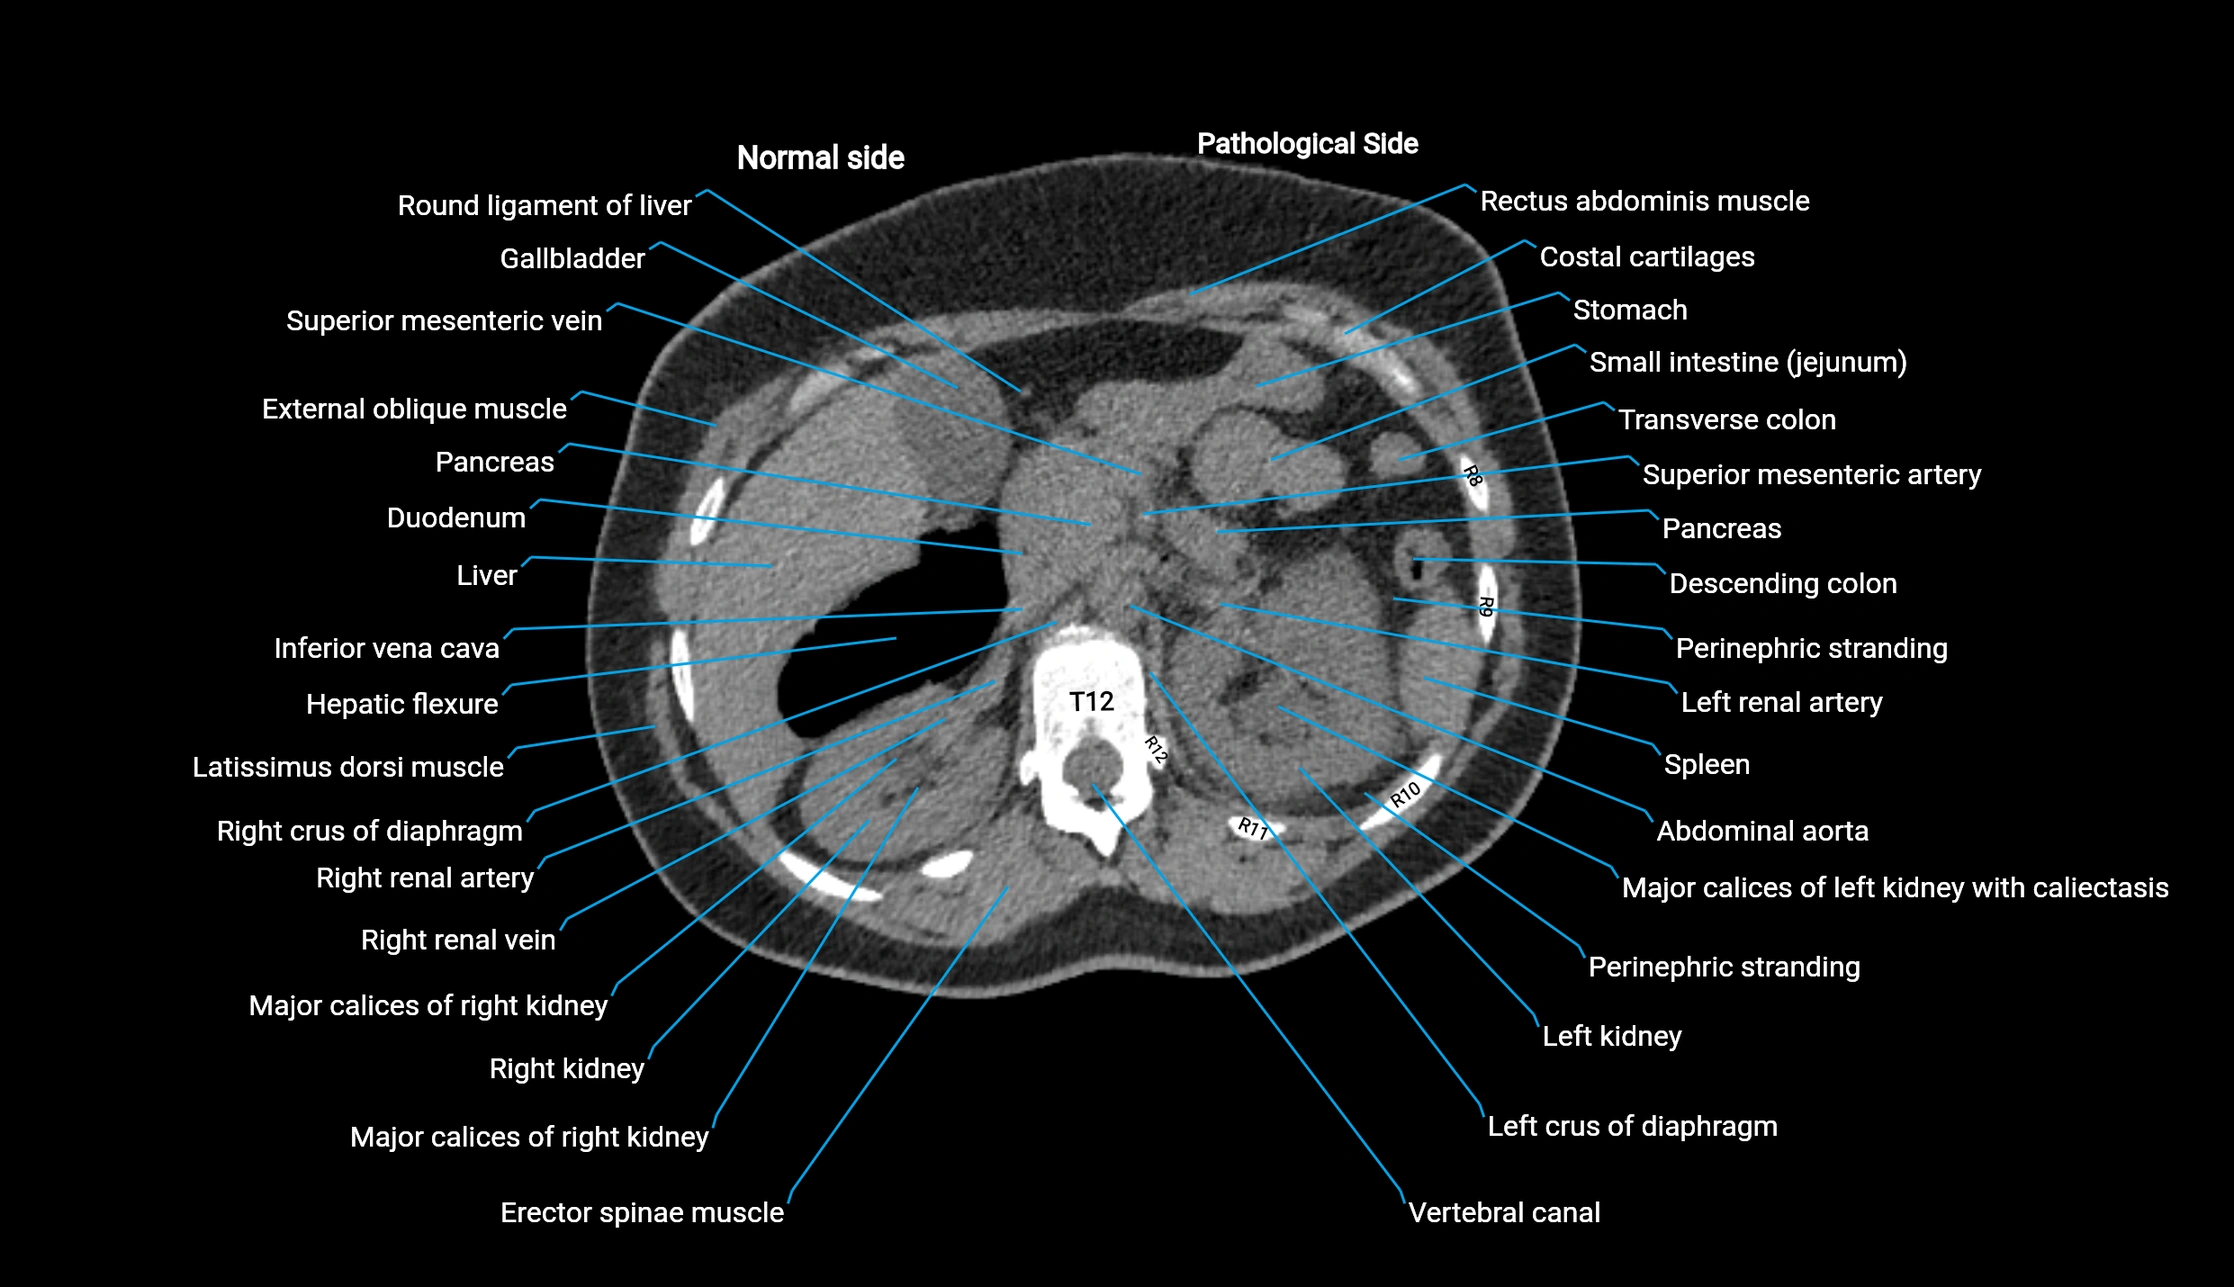

CT image

image